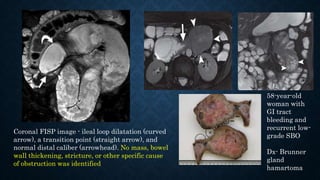

Coronal FISP image - ileal loop dilatation (curved

arrow), a transition point (straight arrow), and

normal distal caliber (arrowhead). No mass, bowel

wall thickening, stricture, or other specific cause

of obstruction was identified

58-year-old

woman with

GI tract

bleeding and

recurrent low-

grade SBO

Dx- Brunner

gland

hamartoma